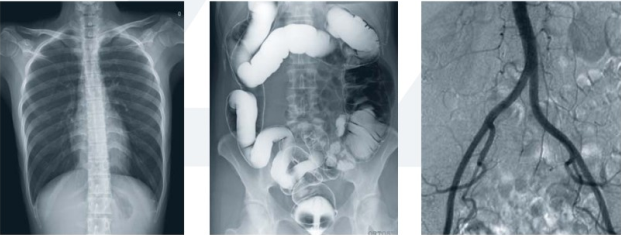

其次,動(dòng)態(tài)dr集常規(guī)拍片、胃腸、透視、造影于一體,真正意義上實(shí)現(xiàn)臨床病灶的快速定位和精細(xì)診斷,大幅提高醫(yī)院的工作效率。

末了,動(dòng)態(tài)dr采集面積大幅面,影像可視范圍為17inchx17inch大尺寸,并且能在連續(xù)動(dòng)態(tài)中全像素點(diǎn)片,極為關(guān)鍵的是還可以進(jìn)行視頻保存,在專家會(huì)診過程中可以回放影像檢查視頻,從而達(dá)到準(zhǔn)確診斷的目的。同時(shí)動(dòng)態(tài)dr還具有全身拼接功能,尤其適用于全脊柱和全下肢攝影,輔助脊柱畸形矯形治療、康復(fù)檢查,為臨床提供高精度圖像。

接下來為大家介紹的動(dòng)態(tài)dr準(zhǔn)確診斷的兩個(gè)實(shí)例。

(1)全身拼接

全身拼接功能是在全景影像拍攝的情況下,拍攝各個(gè)部位的影像,得到的圖像結(jié)果合成一幅全景圖像。動(dòng)態(tài)dr的此功能操作簡單、可自動(dòng)或手動(dòng)拼接,畸變率低,圖像均一無拼接痕跡等特點(diǎn),尤其適用于全脊柱和全下肢攝影,輔助脊柱畸形矯形治療、康復(fù)檢查,為臨床提供高精度圖像。

(2)消化道陰性異物

消化道陰性異物就是在x射線透視的情況下,無法顯示的異物,這個(gè)異物不阻擋x射線,且能夠透視x射線。

一個(gè)成人病人,吃了魚骨卡在喉部,病理表現(xiàn)是嗓子痛、出血;通過用動(dòng)態(tài)dr進(jìn)行消化道吞鋇棉檢查,一口造影劑,一口棉花;如果魚刺比較小,那么在鋇棉經(jīng)過的時(shí)候魚刺就會(huì)掛在鋇棉上,順著造影劑流下去從而達(dá)到治療的目的;如果魚刺比較大,那么鋇棉就會(huì)被掛在魚刺上,停留在魚刺所在位置;這時(shí)動(dòng)態(tài)dr就可以進(jìn)行定位,然后醫(yī)生可以通過定位用胃鏡或耳鼻喉鏡將魚刺取出來。這就是動(dòng)態(tài)準(zhǔn)確診斷或準(zhǔn)確治療的優(yōu)勢。